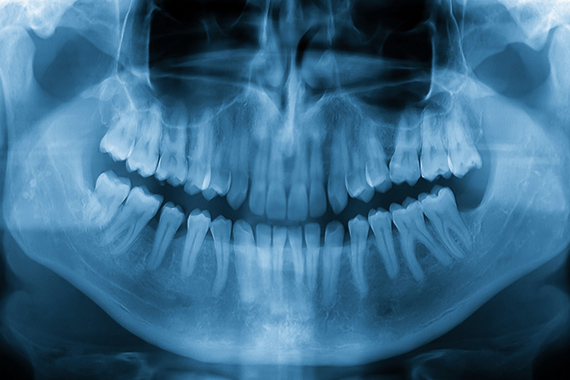

歯科用CT

治療箇所をより正確に特定するために、当院では歯科用CTを使用し、歯や骨の詳細な3Dデータを取得しています。

立体画像で丁寧に検査・診断します

当院では、歯や顎の骨の状態を立体的に把握できる歯科用CTを使用して、より丁寧な検査・診断を実施しています。肉眼では見えにくい部分まで確認しやすく、親知らずの抜歯やインプラント治療、根の治療などにも活用されています。平面的なレントゲンでは見逃しやすい病変や炎症なども、歯科用CT画像なら発見しやすくなり、症状が出る前の小さな変化にも気づきやすくなります。